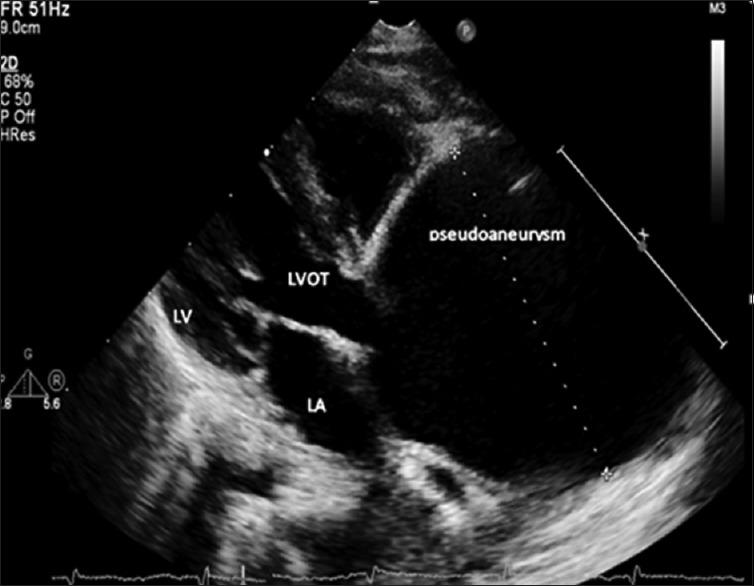

Mycotic pseudoaneurysm of the aorta is a rare and lethal complication of pediatric congenital heart surgery. We report the lethal consequences of recurrent mycotic pseudoaneurysm in an 18-month-old baby, early after subaortic membrane resection. We managed to repair the pseudoaneurysm successfully by replacing the infected ascending aorta using bovine jugular vein graft, but unfortunately, the patient developed new pseudoaneurysm at the site of anastomosis which led to his death. Although prompt diagnosis and surgical management can save the patient life, uncontrolled infection can lead to the recurrence of the problem and lethal results.

主动脉霉菌性假性动脉瘤是小儿先天性心脏手术罕见且致命的并发症。我们报告了一名18个月大婴儿在主动脉下膜切除术后早期复发性霉菌性假性动脉瘤的致命后果。我们通过使用牛颈静脉移植物替换感染的升主动脉成功修复了假性动脉瘤,但不幸的是,患者在吻合部位出现了新的假性动脉瘤,最终导致死亡。尽管及时诊断和手术治疗可以挽救患者生命,但感染控制不佳会导致问题复发并产生致命后果。